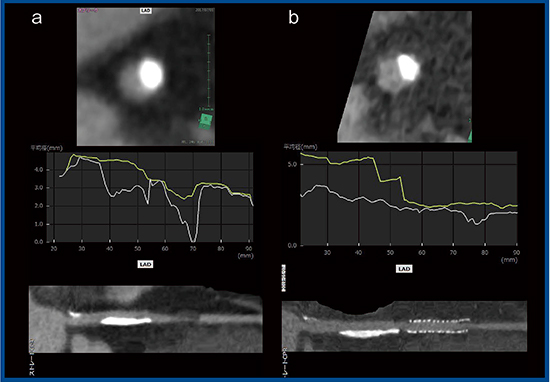

そこで,Aquilion Precisionで3.0mm未満のステントの評価が可能かどうかを検討した。2.5mmのSynergyステントを水槽内に留置し,従来CTとAquilion Precisionで撮影した(図2)。水のCT値は0のため,本来はステント内腔は0となるはずだが,従来CTではブルーミングアーチファクトの影響でCT値は不正確である(図2 a)。一方,Aquilion Precisionでは0になっており,内腔の状態を正確に反映していると考えられる(図2 b)。

図2 従来CT(a)とAquilion Precision(b)のステント描出能の比較